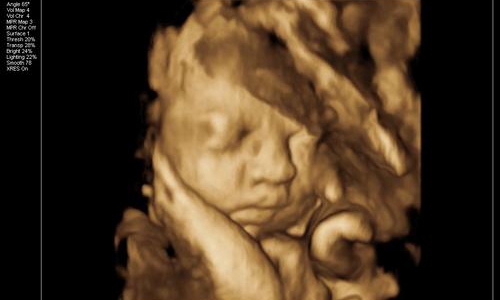

真的是这样吗?专家解答说,其实四维彩照出来的成像与宝宝出生后的模样会有一定出入,以下三张图片告诉你。

1、 胎儿还未发育完全

一般孕妇在正常情况下都是在28周的样子去拍四维,可是你们要知道这个时期的宝宝还没有完全发育成熟。拿苹果举例,从青涩到成熟得经历一段时间,而28周的胎儿就相当于七分熟的苹果。

胎儿的面部脂肪还没有完全堆积,因此从四维看到的脸蛋来说是比较丑的,类似于外星人。头部和身体的占比例大概是2:1,以成年人的视觉来看可不是怪异么。

再者,孕妇拍摄四维的目的,便是排除胎儿面部是否畸形。所以会根据声波成像技术来填充图像,再将口、鼻、眼等细节放大。